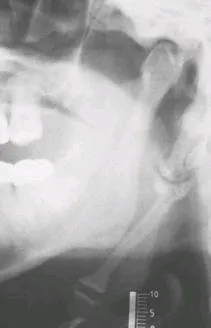

* 全口環口 X 光(pano)或側位顎骨 X 光( lateral-jaw radiographs)

可見莖突延長 或 莖舌骨韌帶複合體礦化

(99-1-10.)一位成年患者主訴吞嚥、轉頭及張口時出現顏面部疼痛,近來也常出現頭痛、耳痛及頭暈之症狀,經放射線檢查發現患者之莖突舌骨韌帶(stylohyoid ligament)有鈣化現象(如 上圖所示),據此您的診斷為下列何者?(A) 亞瑟氏症候群(Ascher syndrome)(B) 貝謝氏症候群(Behçet’s syndrome)(C) 克魯遜氏症候群(Crouzon syndrome)(D) 依格氏症候群(Eagle syndrome)

(92-1-2.)一位成年患者主訴顏面疼痛,特別是在吞嚥、轉頭及張口時,由顎全景 X 光片發現莖突舌骨韌帶鈣化(mineralization of stylohyoid ligament),請問正確診斷為下列何者? (A)亨特氏症候群 (Hunter's syndrome) (B)依格氏症候群 (Eagle syndrome) (C)海耳福德氏症候群 (Heerfordt's syndrome) (D)弗策症候群 (Frey syndrome)